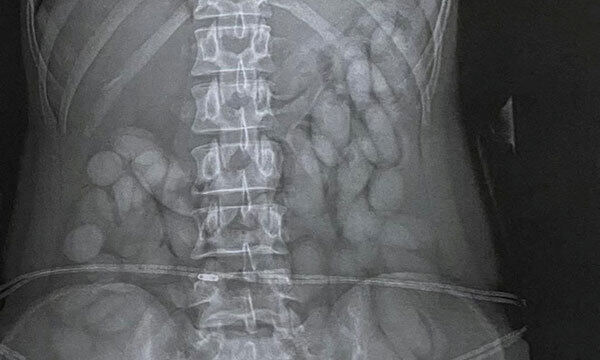

경찰은 브라질 상파울루에서 도착한 이 여성을 병원으로 보내 엑스레이 촬영을 한 결과 뱃속에서 다량의 타원형 캡슐을 확인했다. 아틀렌다 마테 남아공 경찰 대변인은 “첩보에 따라 마약운반책을 기다리고 있다가 이민국 통과 즉시 검거했다”며 “코카인이 담긴 캡슐 60여개를 회수했다”고 말했다. 남아공 경찰에 따르면 지난 2개월간 OR탐보 국제공항에서 체포된 마약운반책은 10명에 달하며 1300만랜드(약 10억원)어치의 마약이 압수됐다.